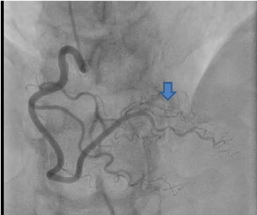

Patient was taken for emergent cardiac catheterization that showed 100% stenosis in proximal left anterior descending artery with TIMI 0 flow (Figure 2 and 3). There were abundant collaterals from RCA to septum (Figure 4). Due to late presentation MI with Q waves on EKG, PCI was deferred. Patient was started on aspirin, clopidogrel, carvedilol, high-intensity statin and unfractionated heparin and was admitted to coronary care unit for further management and observation.

Figure 2. Coronary Angiogram in Right Anterior Oblique Caudal (RAO) view with complete occlusion of LAD as indicated by arrow